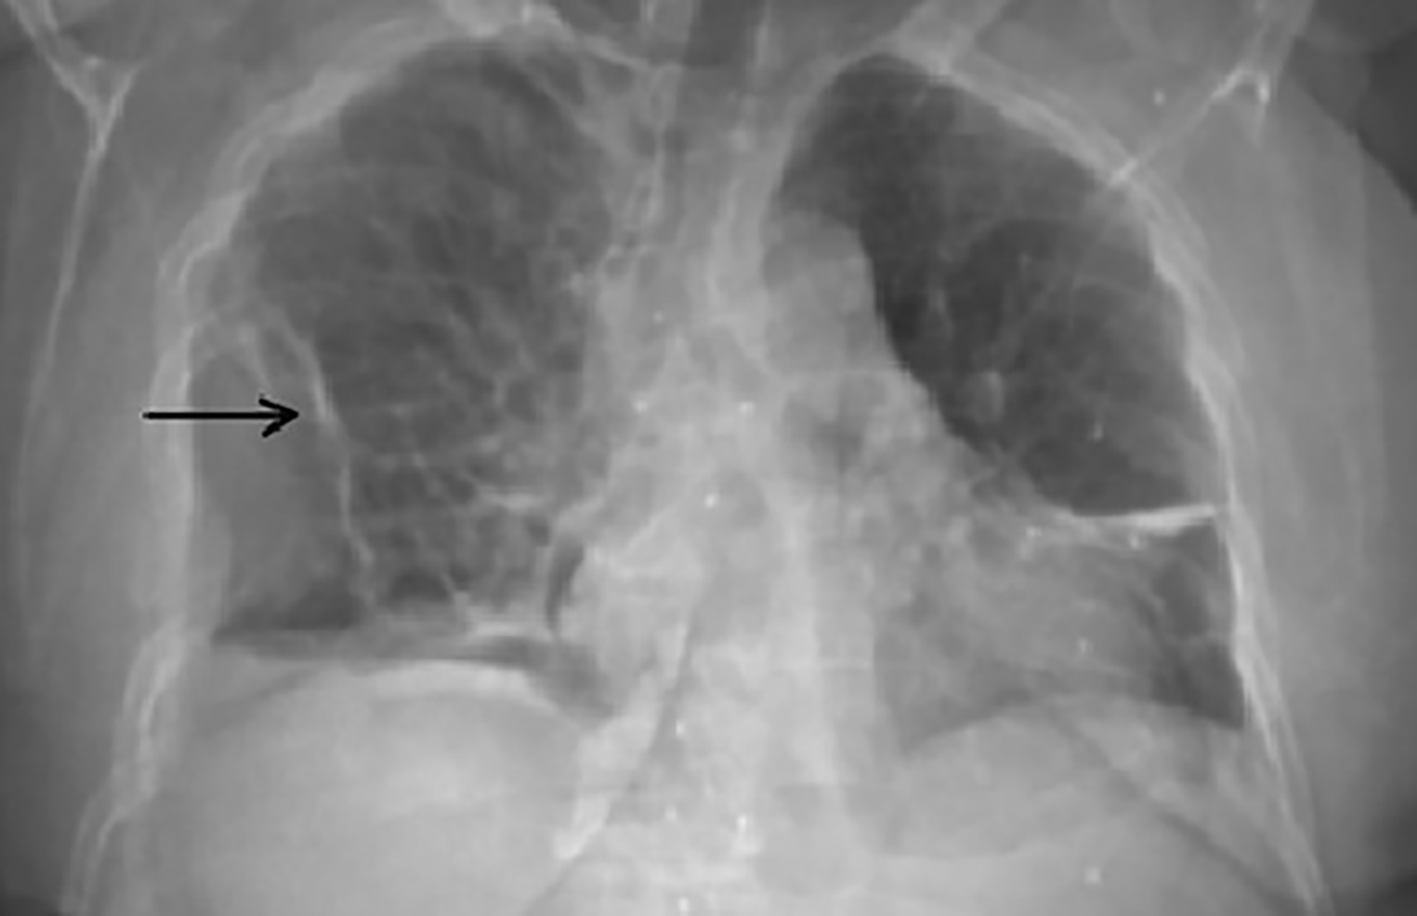

Chest radiography and thoracic computed tomography revealed multiple ribs and sternum fractures leading to a partial pneumothorax on the right side (Figures 1, 2). She also had objective spine fractures localized in the T8, T9 and T10 vertebrae.

Multiple myeloma is an hemopathy with excessive bone resorption, leading to single or multiple osteolytic lesions.4 About 85% of patients with Multiple myeloma show some degree of osteopenia at the moment of diagnosis. The severity of bone destruction is frequently correlated with the tumor burden and the Multiple myeloma prognosis.5 In our case, the rib fractures were the cause of a pneumothorax leading to an acute respiratory failure. These rib fractures were characterized by a periosteal callus which was predominant in the ventral side of the chest. The same appearance of rib fracture has been shown in an autopsy study in fatal child abuse cases.6 It has been suggested that the mechanism of this pneumothorax is due to the bending of the rib against the transverse process, acting as a fulcrum and leading to spontaneous rib fracture. Also, such fractures suggest that the mechanism of injury is not a direct trauma.7 Although, as reported in thoracic injury from blunt force trauma, rib fracture can puncture the lungs and the pleural sac, leading to a pneumothorax, a life-threatening complication.7